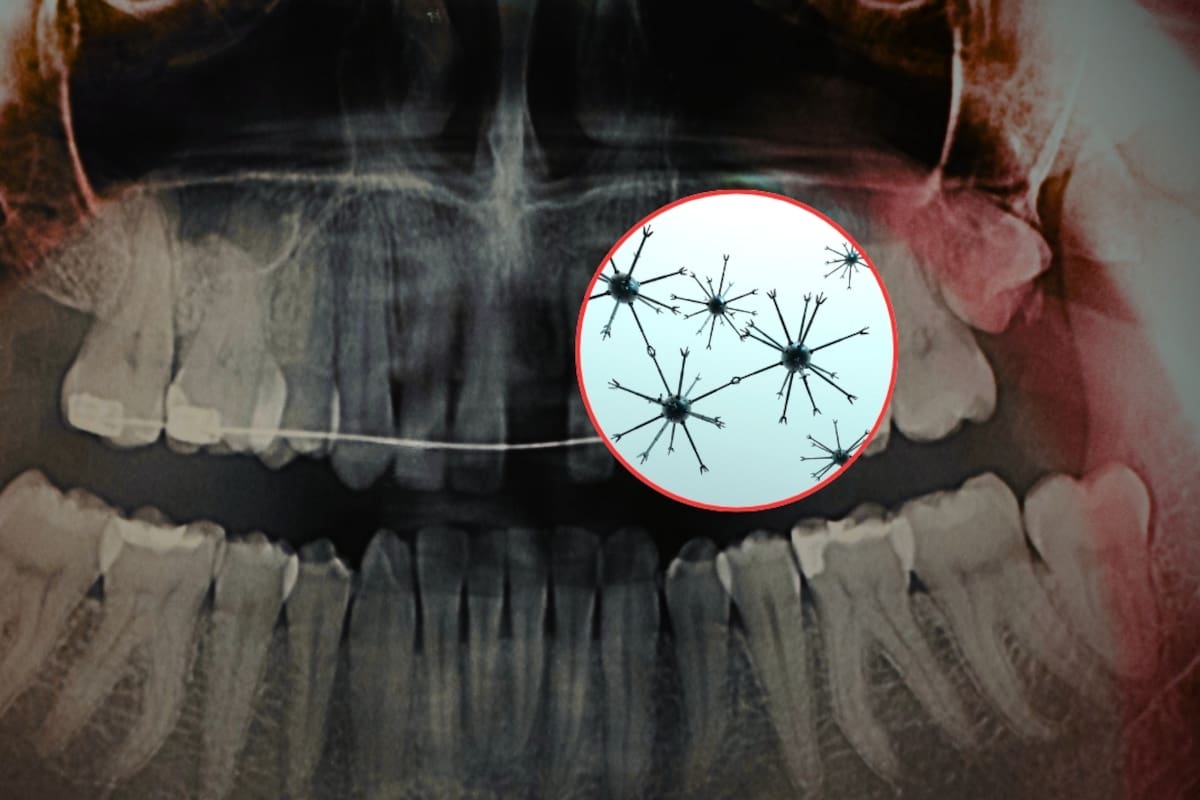

De acuerdo con un estudio publicado en la revista científica Advanced Science y difundido por el Instituto Indio de Ciencias (IISc), en colaboración con la empresa tecnológica Theranautilus, se desarrollaron nanorobots magnéticos llamados Calbots que buscan tratar la sensibilidad dental desde el interior del diente.

Los Calbots son nanorobots magnéticos diseñados para penetrar en los túbulos dentinarios, que son pequeños canales dentro de la dentina que pueden conectar con las terminaciones nerviosas del diente. Cuando estos canales quedan expuestos, se produce la sensibilidad.

Los Calbots miden alrededor de 400 nanómetros y están compuestos por un material biocerámico basado en silicato de calcio. Su funcionamiento se basa en tres pasos principales:

- Guía magnética: se utiliza un campo magnético externo para dirigir los nanorobots hacia los túbulos dentinarios expuestos.

- Penetración profunda: pueden llegar a una profundidad de entre 300 y 500 micrómetros dentro del diente.

- Sellado interno: una vez dentro, se autoensamblan y forman tapones estables similares al cemento, bloqueando los canales que generan la sensibilidad.